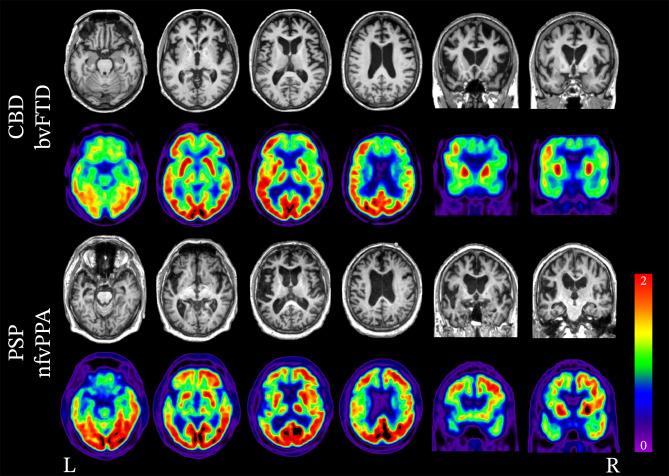

Frontotemporal dementia encompasses a group of clinical syndromes defined pathologically by degeneration of the frontal and temporal lobes. Historically, these syndromes have been challenging to diagnose, with an average of about three years between the time of symptom onset and the initial evaluation and diagnosis. Research in the field of neuroimaging has revealed numerous biomarkers of the various frontotemporal dementia syndromes, which has provided clinicians with a method of narrowing the differential diagnosis and improving diagnostic accuracy. As such, neuroimaging is considered a core investigative tool in the evaluation of neurodegenerative disorders. Furthermore, patterns of neurodegeneration correlate with the underlying neuropathological substrates of the frontotemporal dementia syndromes, which can aid clinicians in determining the underlying etiology and improve prognostication. This review explores the advancements in neuroimaging and discusses the phenotypic and pathologic features of behavioral variant frontotemporal dementia, semantic variant primary progressive aphasia, and nonfluent variant primary progressive aphasia, as seen on structural magnetic resonance imaging and positron emission tomography.

额颞叶痴呆包括一组临床综合征,这些综合征在病理学上由额叶和颞叶的退化定义。从历史上看,这些综合征的诊断一直具有挑战性,从症状出现到首次评估和诊断的平均时间约为三年。神经影像学领域的研究揭示了各种额颞叶痴呆综合征的许多生物标志物,这为临床医生提供了一种缩小鉴别诊断范围和提高诊断准确性的方法。因此,神经影像学被认为是评估神经退行性疾病的核心研究工具。此外,神经退行性变的模式与额颞叶痴呆综合征的潜在神经病理学基础相关,这可以帮助临床医生确定潜在病因并改善预后。这篇综述探讨了神经影像学的进展,并讨论了在结构磁共振成像和正电子发射断层扫描上观察到的行为变异型额颞叶痴呆、语义变异型原发性进行性失语症和非流利变异型原发性进行性失语症的表型和病理特征。